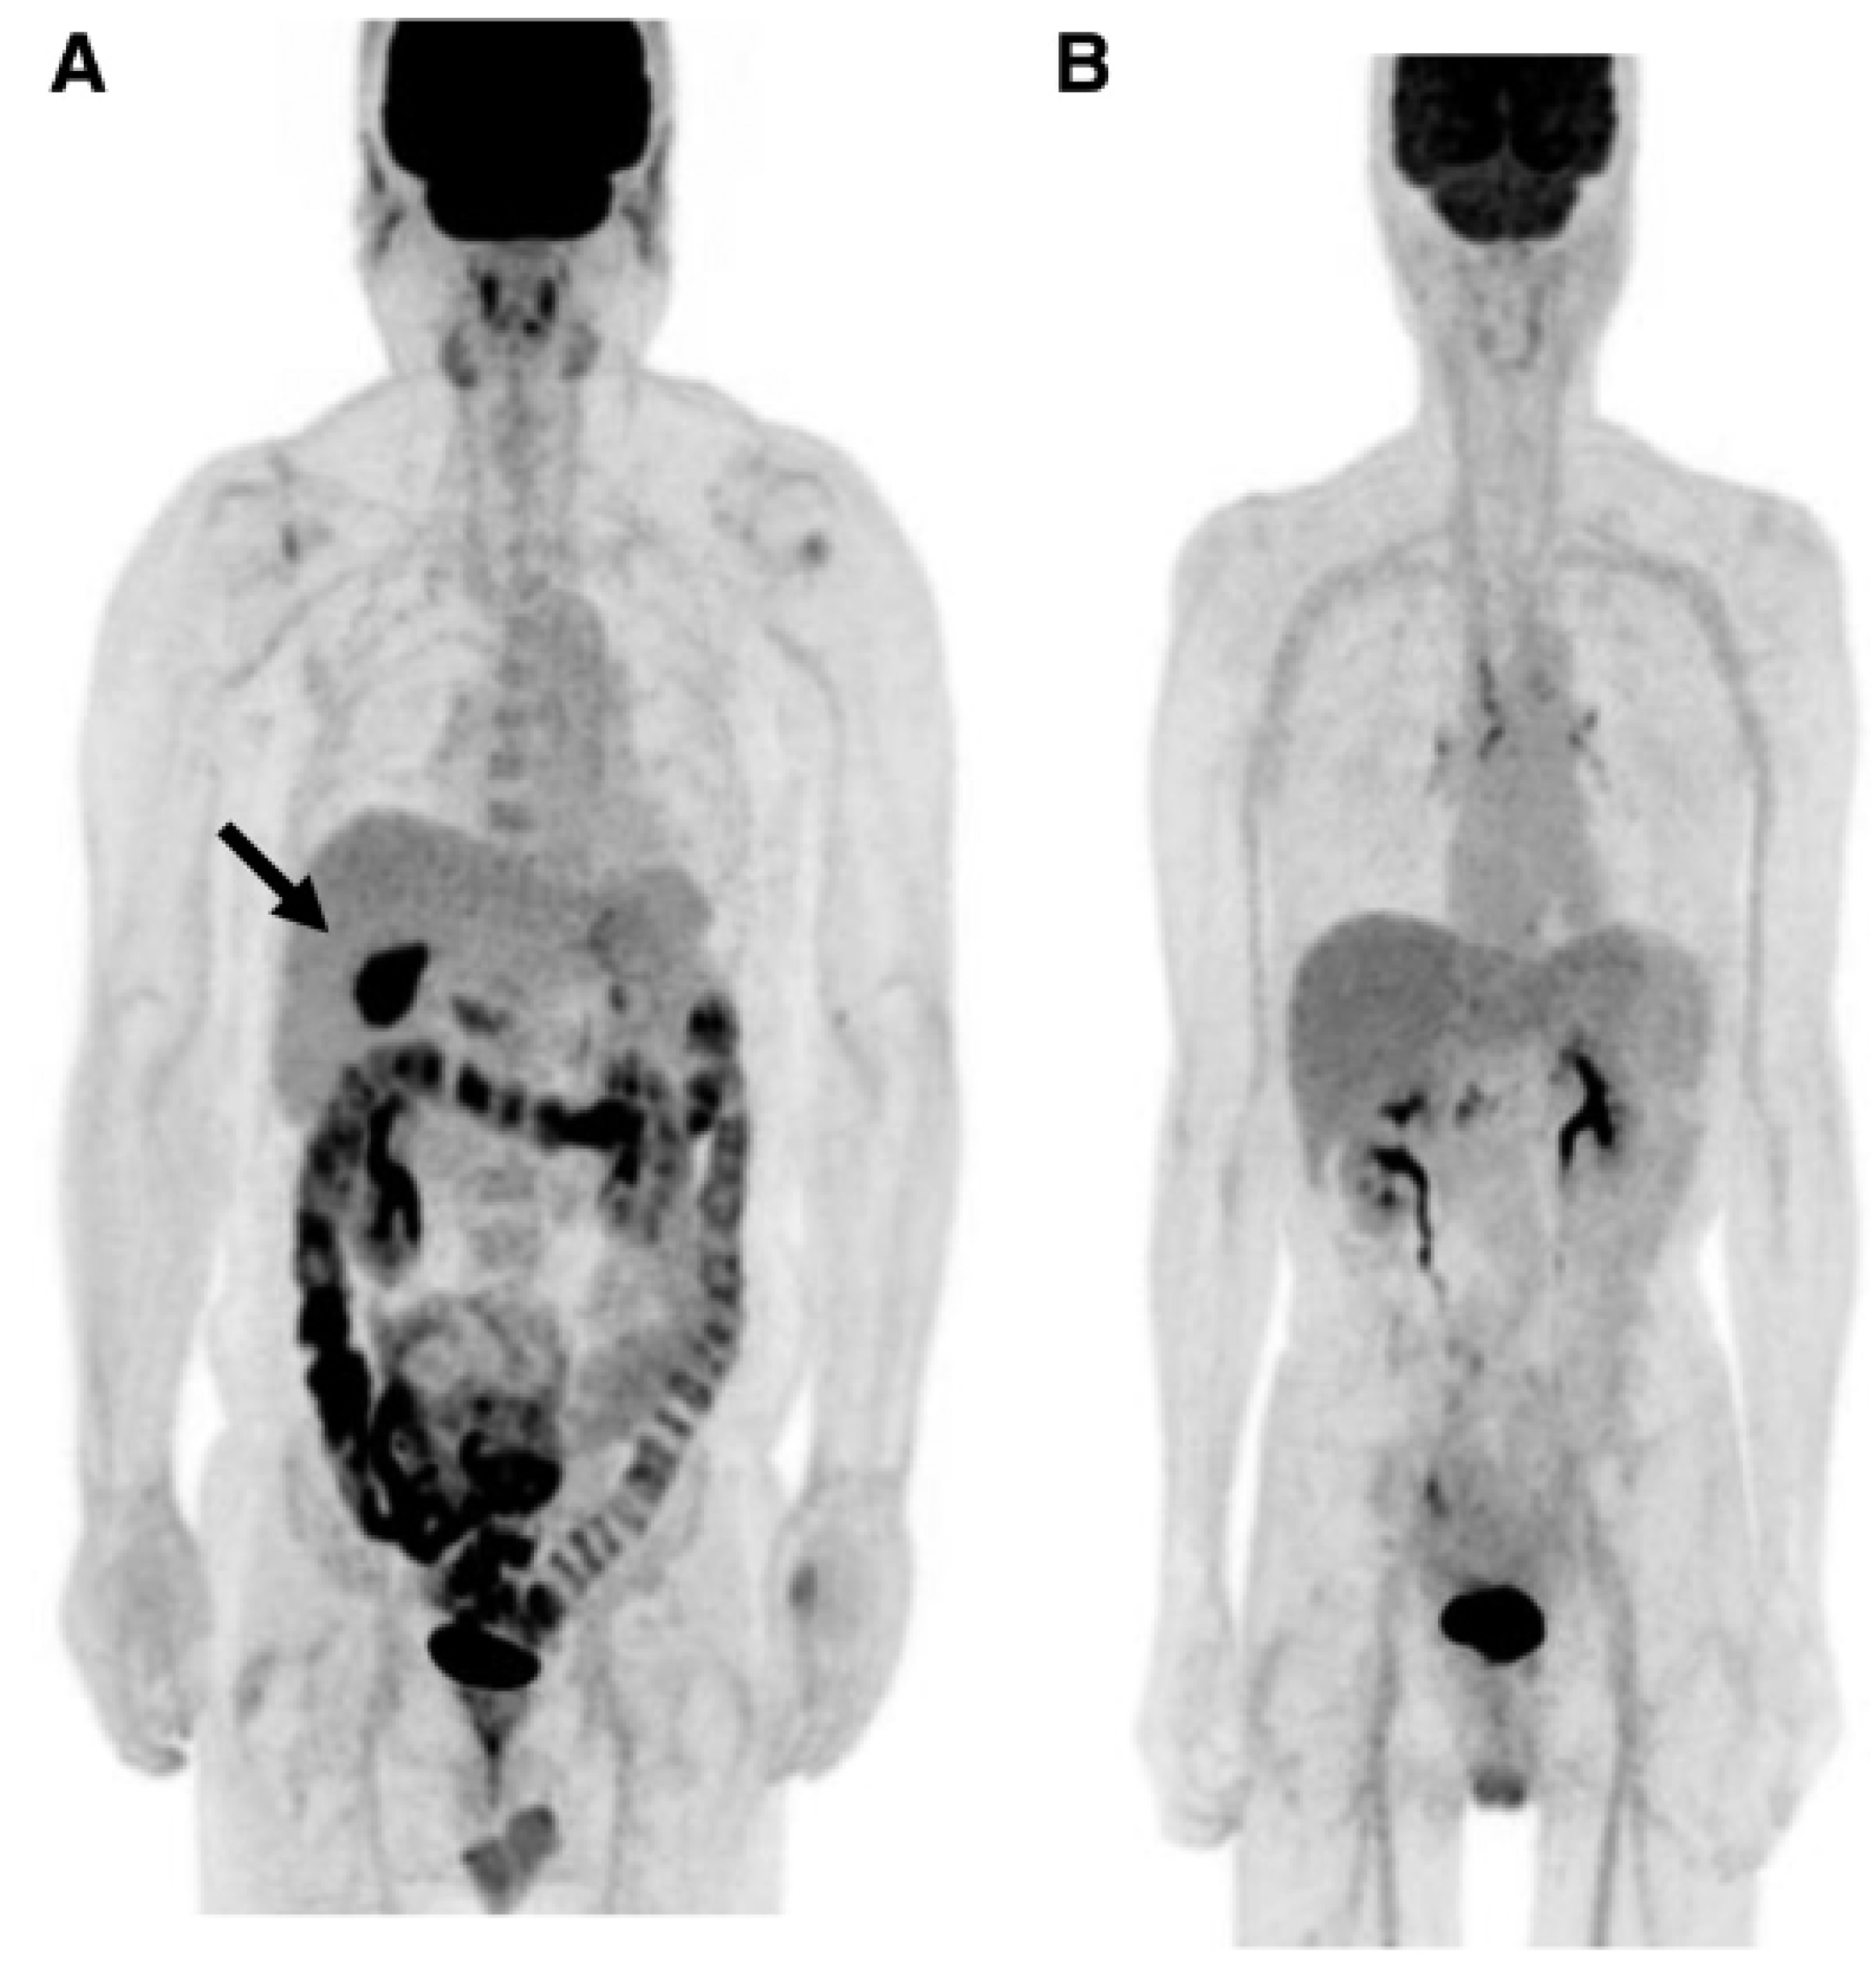

Morita and coworkers [171], by using positron emission tomography (PET)-MRI, recently found that the maximum standardized uptake value (SUVmax) of F18-FDG in the intestine (jejunum, ileum, and right or left hemicolon) of metformin-treated diabetics was higher than that of the control group. More importantly, the study permitted to differentiate the SUVmax of the intestinal wall from that of the intestinal lumen. The SUVmax of the intraluminal space in metformin-treated diabetics was greater than that of the controls (Figure 2). On the contrary, the SUVmax of the intestinal wall was similar in both groups [171]. A temporarily increased accumulation of the injected tracer seems to be observed (Figure 3) also in the liver of metformin-treated diabetics up to 48 h after interruption of the oral uptake of the drug [171,172,173], suggesting a persisting uptake of the radioactive glucose mediated by circulating insulin as consequence of the “metabolic starvation”(?) induced by the biguanide.

Figure 2.

PET-images taken 60 min after intravenous administration of F18-FDG in a diabetic patient treated with metformin (A) and in a control patient (B). In (A), radioactivity has accumulated in the last portion of the ileum and in the colon (right hemicolon, stronger than left hemicolon). The indication for the study was that gall bladder cancer was confirmed by the accumulation of the tracer in the gallbladder (arrow). From Morita Y et al. [171].

Figure 3.

PET scan was performed in diabetics at different times after interruption of metformin therapy. In patient 4, interruption time was shorter than 48 h and showed strong accumulation of the tracer in the colon. From Schreuder N et al. [173].